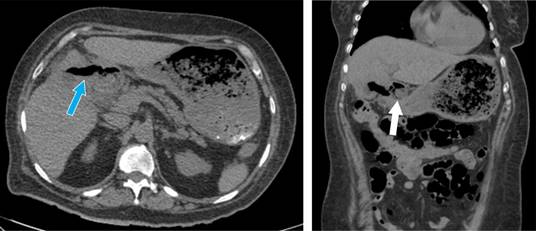

Por hallazgos a través de imagen se sospecha de fístula colecistogástrica, se programa para colecistectomía abierta. Observando como hallazgos, proceso adherencial importante, vesícula biliar escleroatrófica, se evidencia fístula colecistogástrica. Se procede a realizar gastrorrafia y extracción de lito de 2 × 3 cm, y cierre primario de la misma. Para mantener derivado el píloro, se optó por colocar una sonda nasoyeyunal. Se coloca sonda de colecistostomía (Figura 3).

En el postquirúrgico se inicia nutrición parenteral, posteriormente al quinto día postquirúrgico se realiza tomografía axial computarizada (TC) con contraste oral sin evidencia de fuga de medio de contraste (Figura 4), se decide iniciar vía oral, se egresa una semana después de la cirugía.